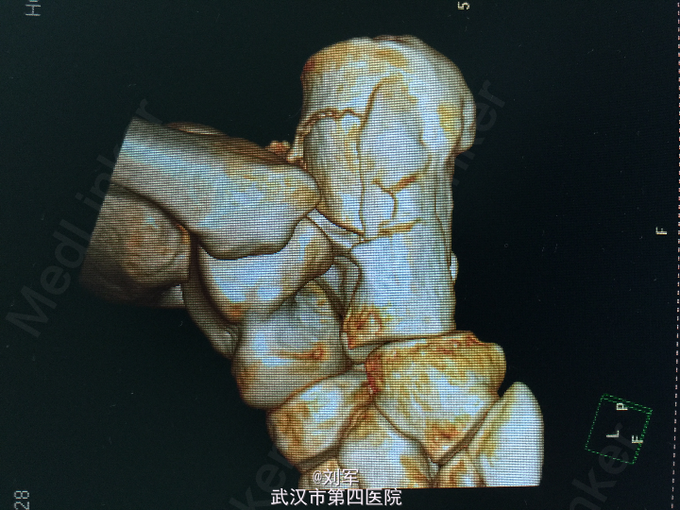

左足跟肿胀,瘀斑,局部压痛及叩痛。左踝活动受限。足趾血运可,感觉存在。左跟骨CT平扫+三维重建:跟骨粉碎性骨折。

左跟骨粉碎性骨折。 入院后完善检查,入院后第六天行开放复位内固定术。

跟骨骨折为创伤骨折常见病,多因高处坠下,足跟着地致伤。根据跟骨CT平扫+三维重建检查,决定治疗方案。